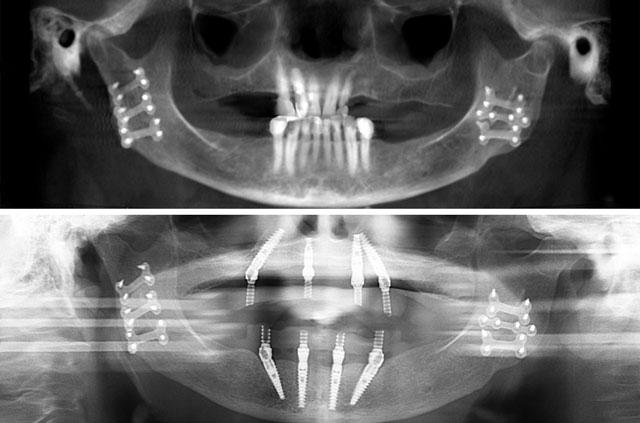

Real before-and-after results from single-tooth implants, All-on-4, All-on-6, and full-arch reconstruction cases.

Each case demonstrates the transformative power of dental implants, from single tooth replacement to full-arch restoration. Our All-on-4 Teeth-In-A-Day technique provides immediate results and long-term stability.

All-on-4 is a revolutionary dental implant technique that uses just four strategically placed implants to support a full arch of replacement teeth. The posterior implants are angled at 30-45 degrees to maximize bone contact and avoid anatomical structures like the maxillary sinus or inferior alveolar nerve. This innovative approach allows for immediate loading with a temporary prosthesis, providing same-day teeth and eliminating the need for lengthy healing periods between procedures.